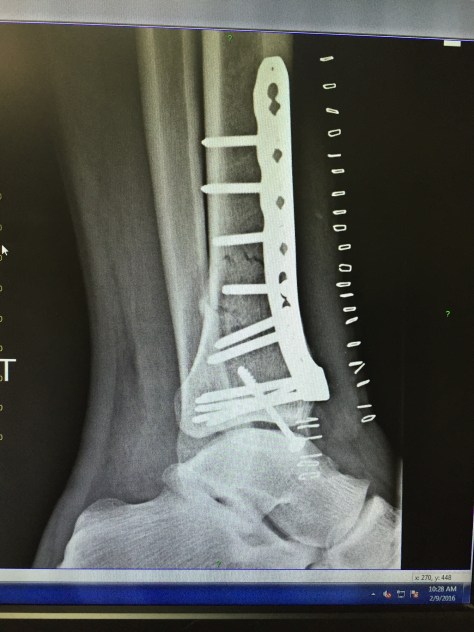

After being admitted to St. John’s Medical Center, I had the privilege of having Dr. Heidi Jost as the surgeon who repaired my broken leg. As it turned out, my tibia was broken into 22 pieces and she did an exceptional job putting everything in place and giving  me the opportunity for a full recovery.  I spent a total of four nights in the hospital, including Super Bowl Sunday, where I “hosted” one of the more expensive four person “party’s” ever.